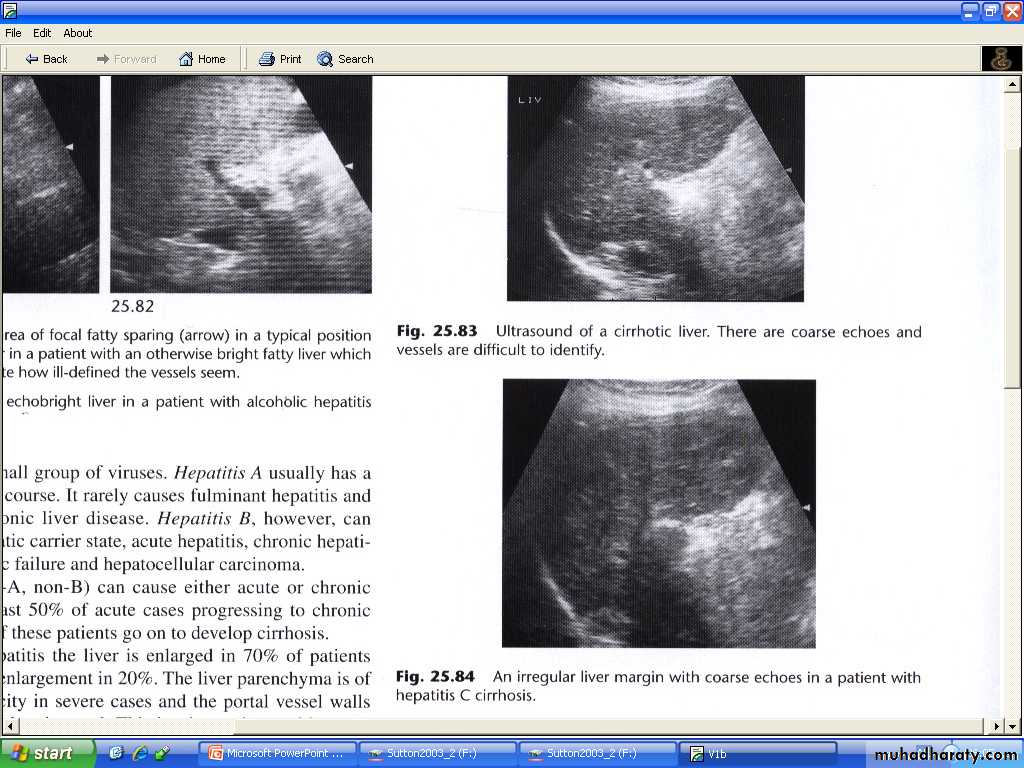

Cirrhosis of the liver and portal hypertension:

The signs of cirrhosis of liver at CT and US are reduction in the size of Rt lobe of the liver and irregularity of liver surface , together with splenomegaly .

Liver texture at US may be diffusely abnormal while on CT appears normal until late in the disease.

Viral hepatitis :

In acute viral hepatitis the liver is enlarged in 70%, splenic enlargement in 20% of cases.By US : liver parenchyma usually normal and decrease echogencity in severe cases and portal vessels more echogenic than normal. GB wall thickened may also be observed.

In Sever chronic hepatitis there is increase echogencity of the liver parenchyma undifferentiated from fatty infiltration ,